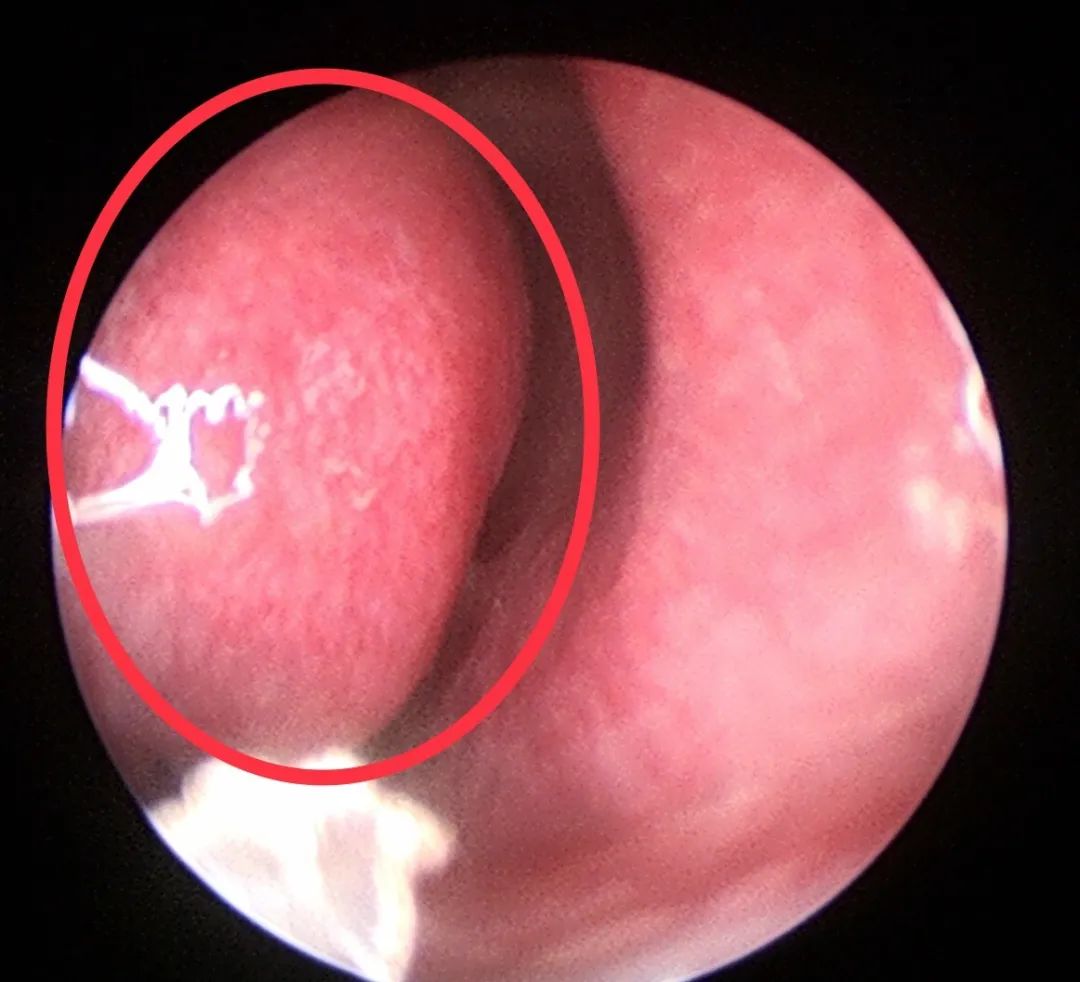

其实,你们看到的这两坨肉,是双侧鼻腔的下鼻甲,就是我们在鼻腔“门口”看到的“肿肿”的肉。

这是每个人都有的,只是每个人的下鼻甲大小不一样而已。

这个下鼻甲其实在你的有生之年就存在了,只是你没见过它的“真面目”而已,有的人怕这坨肉会变“癌”,强烈要求医生帮他切掉,斩草除根。

下鼻甲在我们人体里起到一个非常重要的作用:参与鼻阻力的形成、加温加湿等。

下鼻甲黏膜内的容量血管交替性和规律性的收缩和扩张,调控着鼻周期的变化,促使睡眠时反复翻身,有助于解除疲劳。

既然下鼻甲是我们人体里的一个正常器官,但是很多人还是不放心,希望医生能给他用点药,把他消肿了才放心。